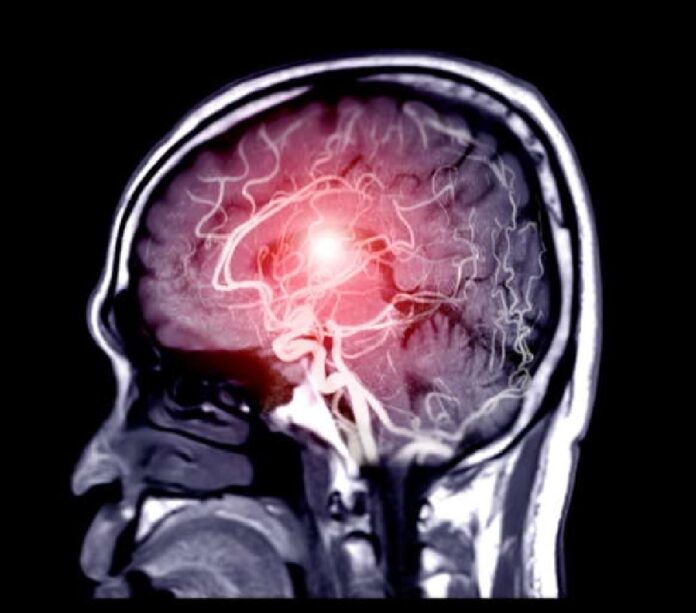

È stato il tempo, in tutti i sensi, a salvare la vita di un crocerista giunto nei giorni scorsi presso l’azienda ospedaliera universitaria di Messina a seguito di un malore. La nave su cui stava trascorrendo una vacanza doveva ripartire dal porto di Messina, ma le avverse condizioni meteo hanno determinato uno stop non programmato. Un imprevisto che, in tale circostanza, si è rivelato una salvezza. Appena giunto in pronto soccorso il paziente presentava un’emiparesi sinistra con impossibilità a camminare ed è stato subito accolto dalla stroke unit, guidata dal Prof. Antonio Toscano.

Qui è stato sottoposto a tutti gli accertamenti necessari per conoscere le origini dell’evento ischemico e dare indicazione all’intervento di trombectomia meccanica, eseguito dall’équipe della UOC di Neuroradiologia Interventistica, diretta dal prof. Sergio Vinci. Si tratta della procedura endovascolare che consente di liberare i vasi ostruiti e per la quale l’AOU è centro di riferimento nella rete provinciale dello stroke. Infatti, nelle ore successive alla trombectomia, il paziente ha recuperato perfettamente e ha ripreso a camminare regolarmente.